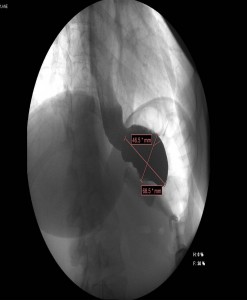

Tránsito esofagogastroduodenal: Banda gástrica malposicionada, localizada aproximadamente a 5-6 cm de la unión esofagogástrica con ángulo phi aumentado de 70º (normal de 4 a 58º). Marcada dilatación del bolsón proximal, con paso enlentecido, filiforme del contraste a través de la banda, no objetivándose paso distal hasta los 10 minutos y persistiendo más allá de los 45 minutos del comienzo del estudio.